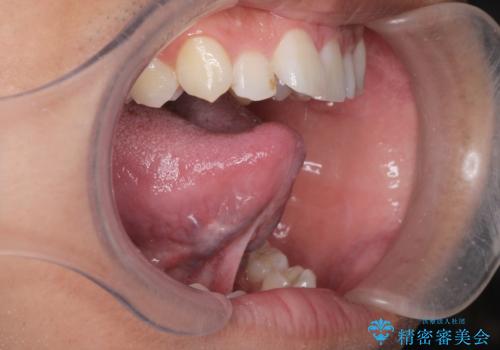

舌の可動域は広がりますが舌の訓練を行わないと滑舌は良くなりません。